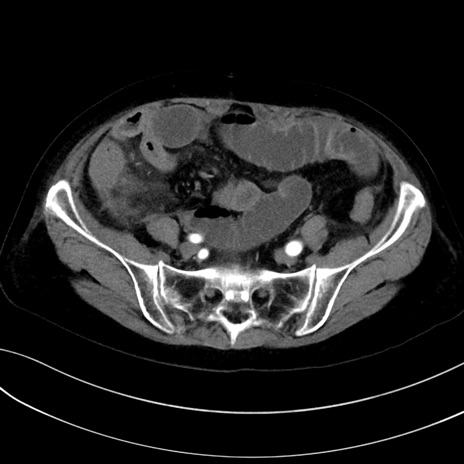

症例13 CT(横断像)1日半後

(冠状断像)1日半後